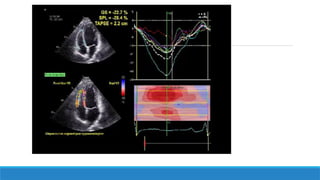

♣ Valeurs normales:

 Longitudinal (négatif): -19,9±5,3% -20%

 radial(positif): +34,4±11,4%

circonférentiel(négatif): -20,3±3,6%

♣ Pic de Strain:

Télésystolique (juste après la fermeture de la valve aortique)

augmente de la base vers l’apex (strain longitudinal)

Interprétation du 2D Strain